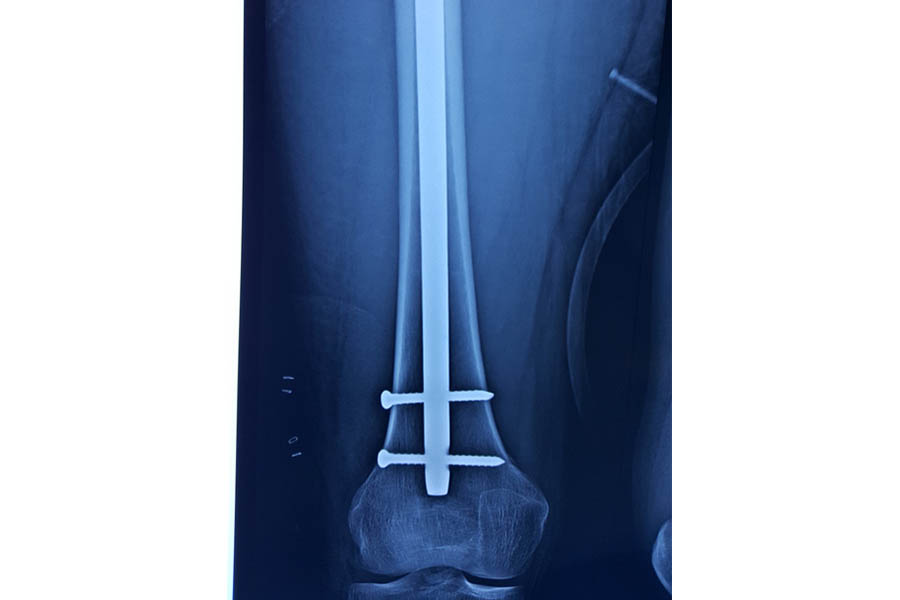

Trauma